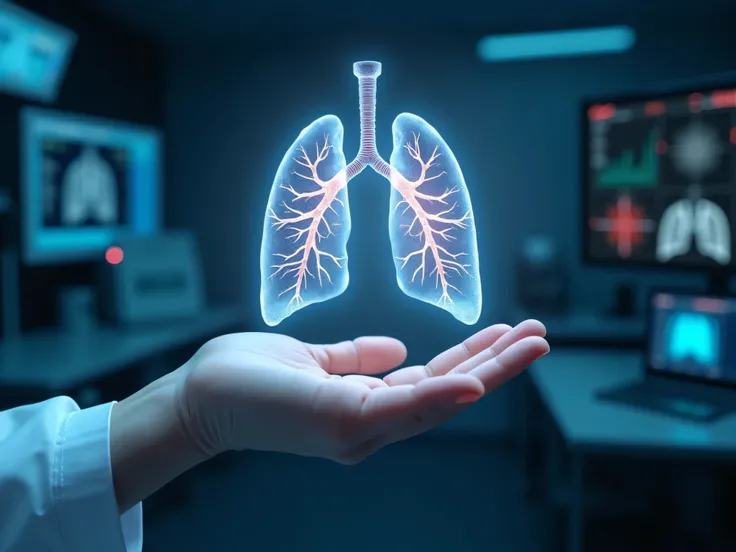

Make a folder about bacterial pneumonia

Make a folder about bacterial pneumonia

Make a folder about bacterial pneumonia